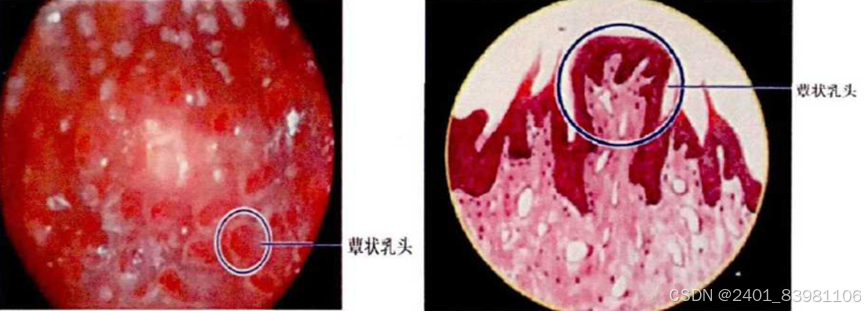

三:乳头分类识别

让患者口含具有苦味强调的标准样品,通过标注注释识别分类(基于深度学习的机器图像识别)如下时一种基于卷积神经网络的机器学习图像处理方法示例:(深度学习方法在乳头客观化方面缺乏突破)

操作:训练有素的操作员对舌头的特定部位进行视觉识别和手动计数(自动图像分析方法);